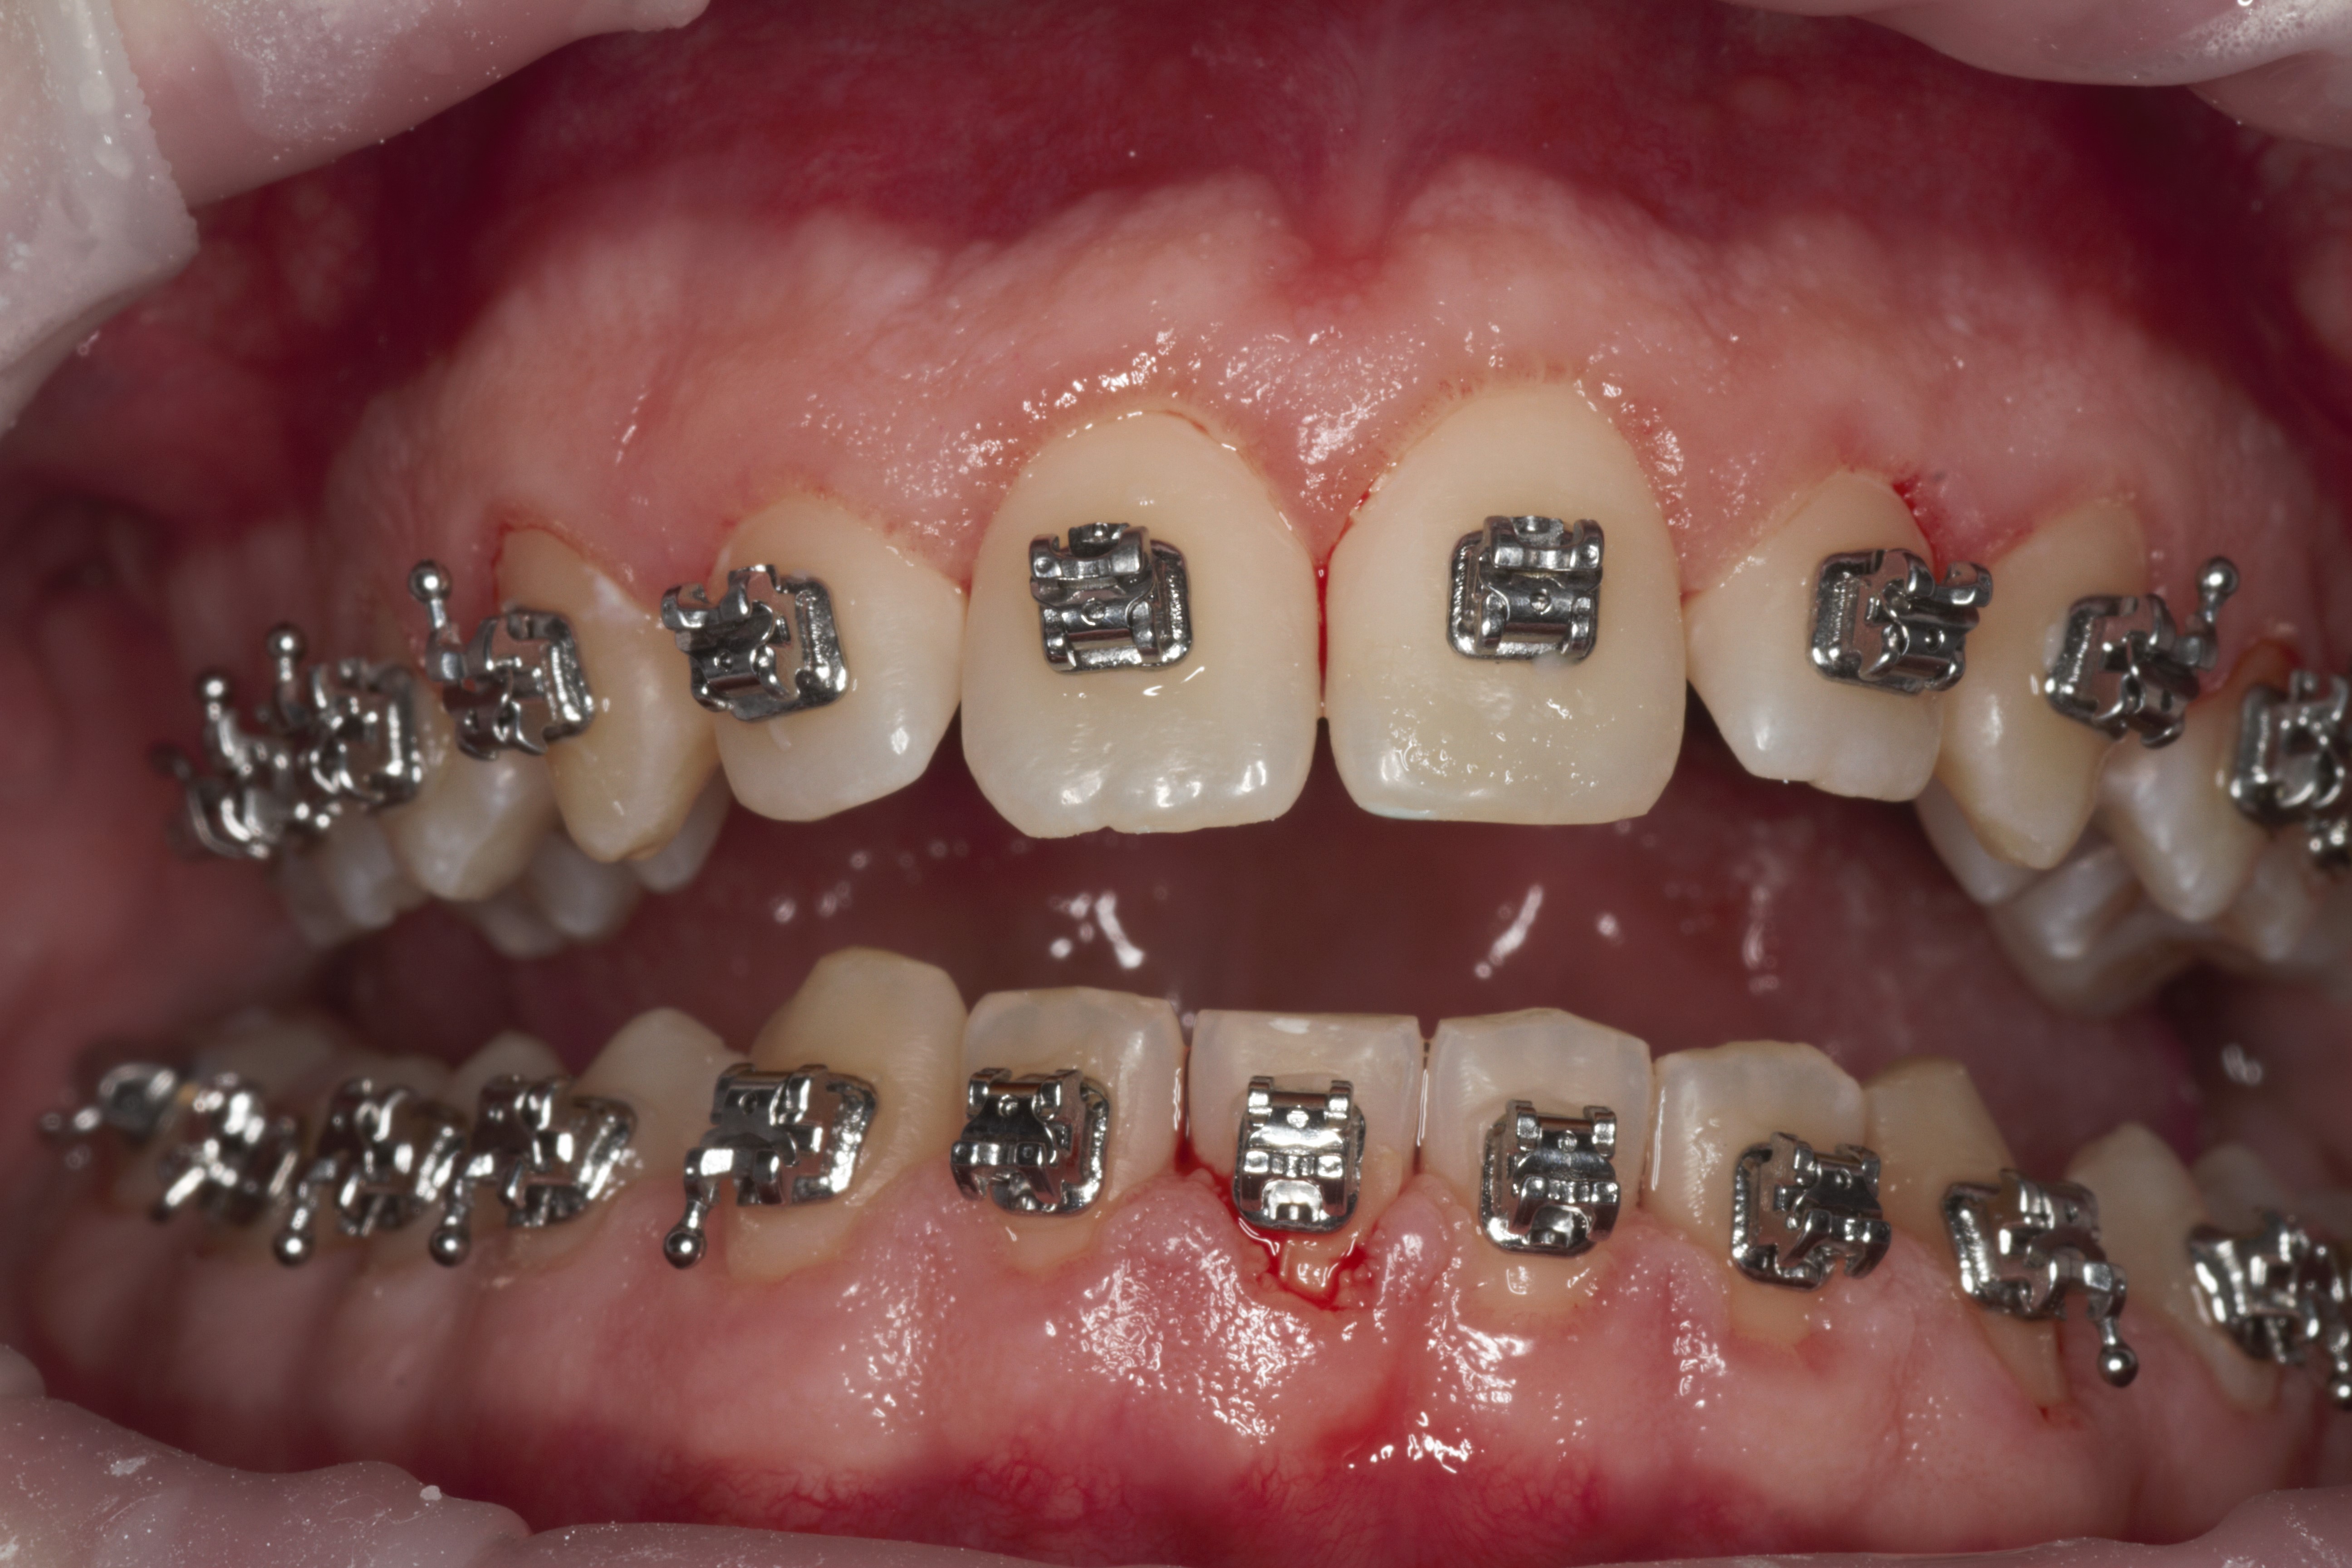

- Эстетическая реставрации жевательной и фронтальной группы зубов современными пломбировочными материалами, диагностика кариеса на ранних этапах развития, предупреждение образования вторичного кариеса в области запломбированных зубов

- Подготовка зубов к ортопедическому и ортодонтическому лечению, с учетом назначенного плана лечения